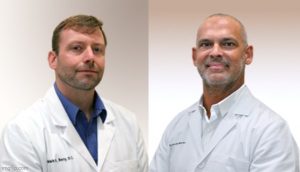

Dr. Rodolfo Alfonso, D.C.

Dr. Mark N. Berry, D.C.

Sunset Chiropractic and Wellness